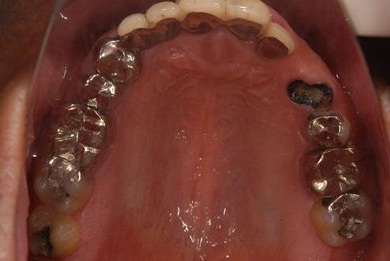

| 性別/年齢 | 男性 / 46歳 | ||||||||||||||||||||||||||||||||

| 治療内容 | インプラント2本(抜歯即日スピードインプラント)、ハイブリッドセラミック2本 | ||||||||||||||||||||||||||||||||

| 総治療費 | 456,750円 | ||||||||||||||||||||||||||||||||

| 治療期間 | 7ヶ月 |